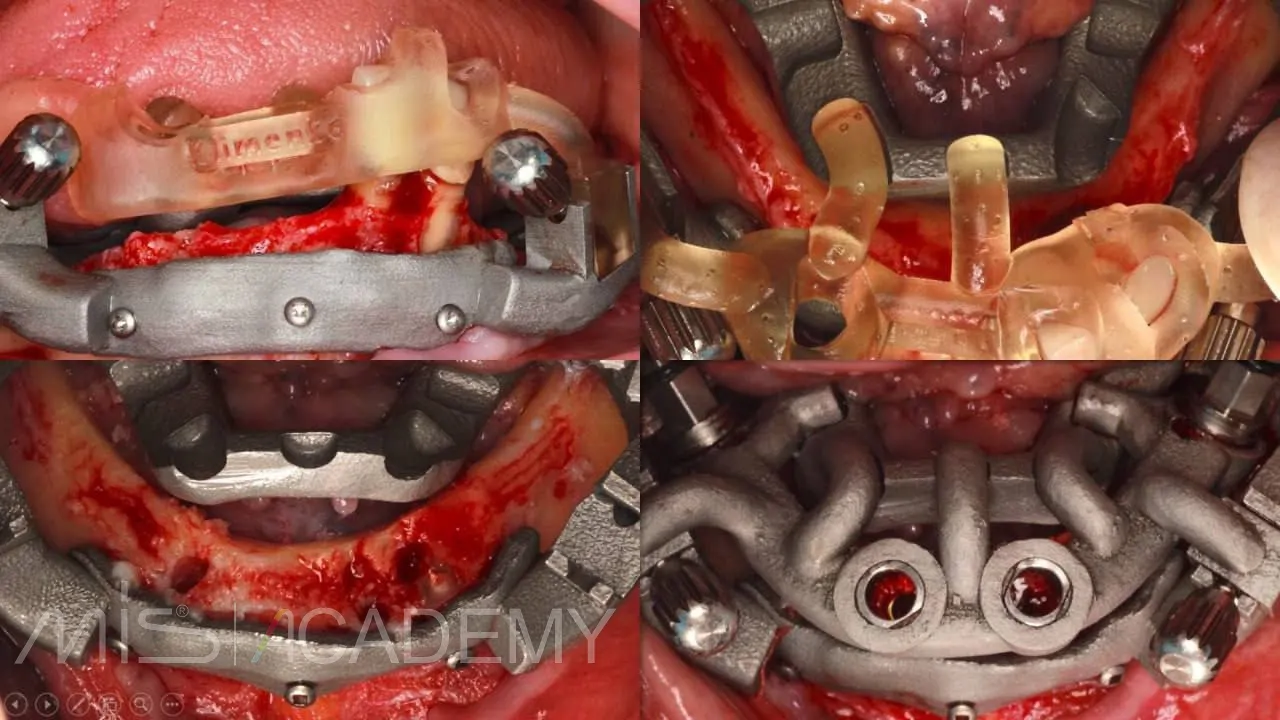

— Multifix на 4-х MIS C1.

— Коннекты во фронте.

— 30 градусов МЮ дистально.

— Навигация полнопротокольная, разборная, накостная.

— Нагрузка немедленная, внутриротовая сварка.